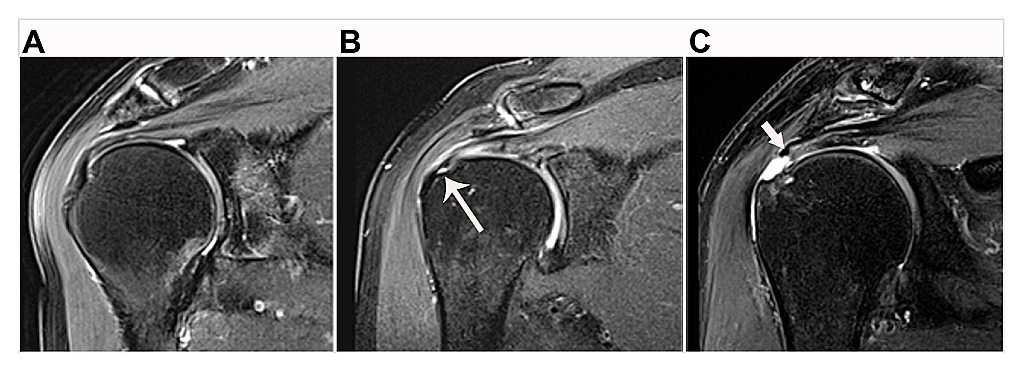

Rotator Cuff ImagingImaging is central for establishing the clinical diagnosis and prognosis for patients presenting with either traumatic acute-onset shoulder dysfunction or non-traumatic shoulder disorders which are not self-limited [22,44,45]. Magnetic resonance imaging (MRI) is the leading imaging modality in the United States to provide definitive imaging evaluation of patients with symptomatic shoulder dysfunction and is a valid and reliable method for diagnosing and characterizing the pattern of RC tear (Figure 1) [20,42,46–48]. MRI also provides concurrent prognostic information about the degree of intramuscular fatty infiltration associated with RC tear, a critical factor that influences orthopaedic surgeons’ clinical decision-making regarding patients’ eligibility to receive RC repair (RCR) surgery (Figure 2) [20,42,46–50]. RC tear is associated with structural changes in the corresponding muscle belly related to intramuscular proliferation of adipose cells and inflammation, fibrosis and apoptosis of myofibers leading to global muscle atrophy and dysfunction [51–53]. Animal and human models of RC tear show that intramuscular fatty infiltration is inversely related to muscular contractile force at the rotator cuff and does not improve after RCR surgery [20,51,54]. During initial steps of pre-operative evaluation, imaging metrics of RC muscle quality are critical, as advanced RC intramuscular fatty infiltration is a relative contraindication to RCR surgery and is associated with poor postsurgical outcomes [46,48–50].

Figure 1. Examples of rotator cuff tendon classification on magnetic resonance imaging. (A) Supraspinatus tendon shows no sign of tear. (B) Partial-thickness tear of the supraspinatus tendon at its greater tuberosity humeral footprint (long arrow). (C) Full-thickness tear of the supraspinatus tendon with medial retraction of the tendon edge (short arrow) away from the greater tuberosity humeral footprint.